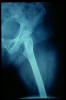

Fractura intertrocantérea de fémur, osteosíntesis